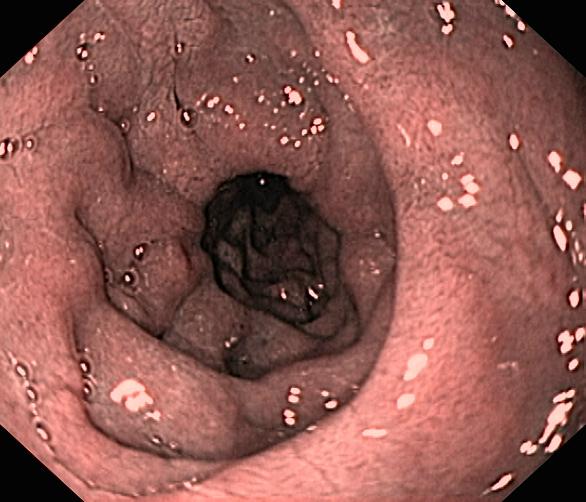

Celiakia